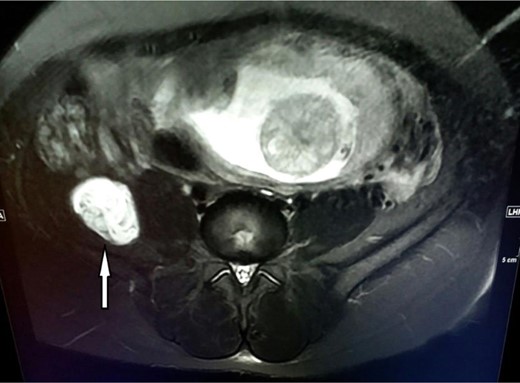

A 28-year-old and 14 weeks pregnant patient presented to general surgery polyclinic with severe pain on her back and right flank. Physical examination revealed tenderness on right lower quadrant of the abdomen, right groin area and right thigh. Ultrasonographic evaluation revealed a lesion showing hypoechoic 46 × 39 mm mass with heterogeneous wall structure on the iliacus muscle at the level of anterosuperior region of the right crista ilica. In magnetic resonance imaging, this lesion was diagnosed as HC (Fig. 1).